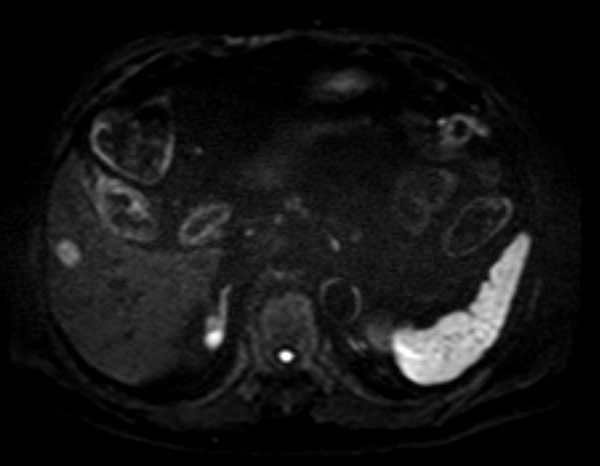

Axial Diffusion (b800)